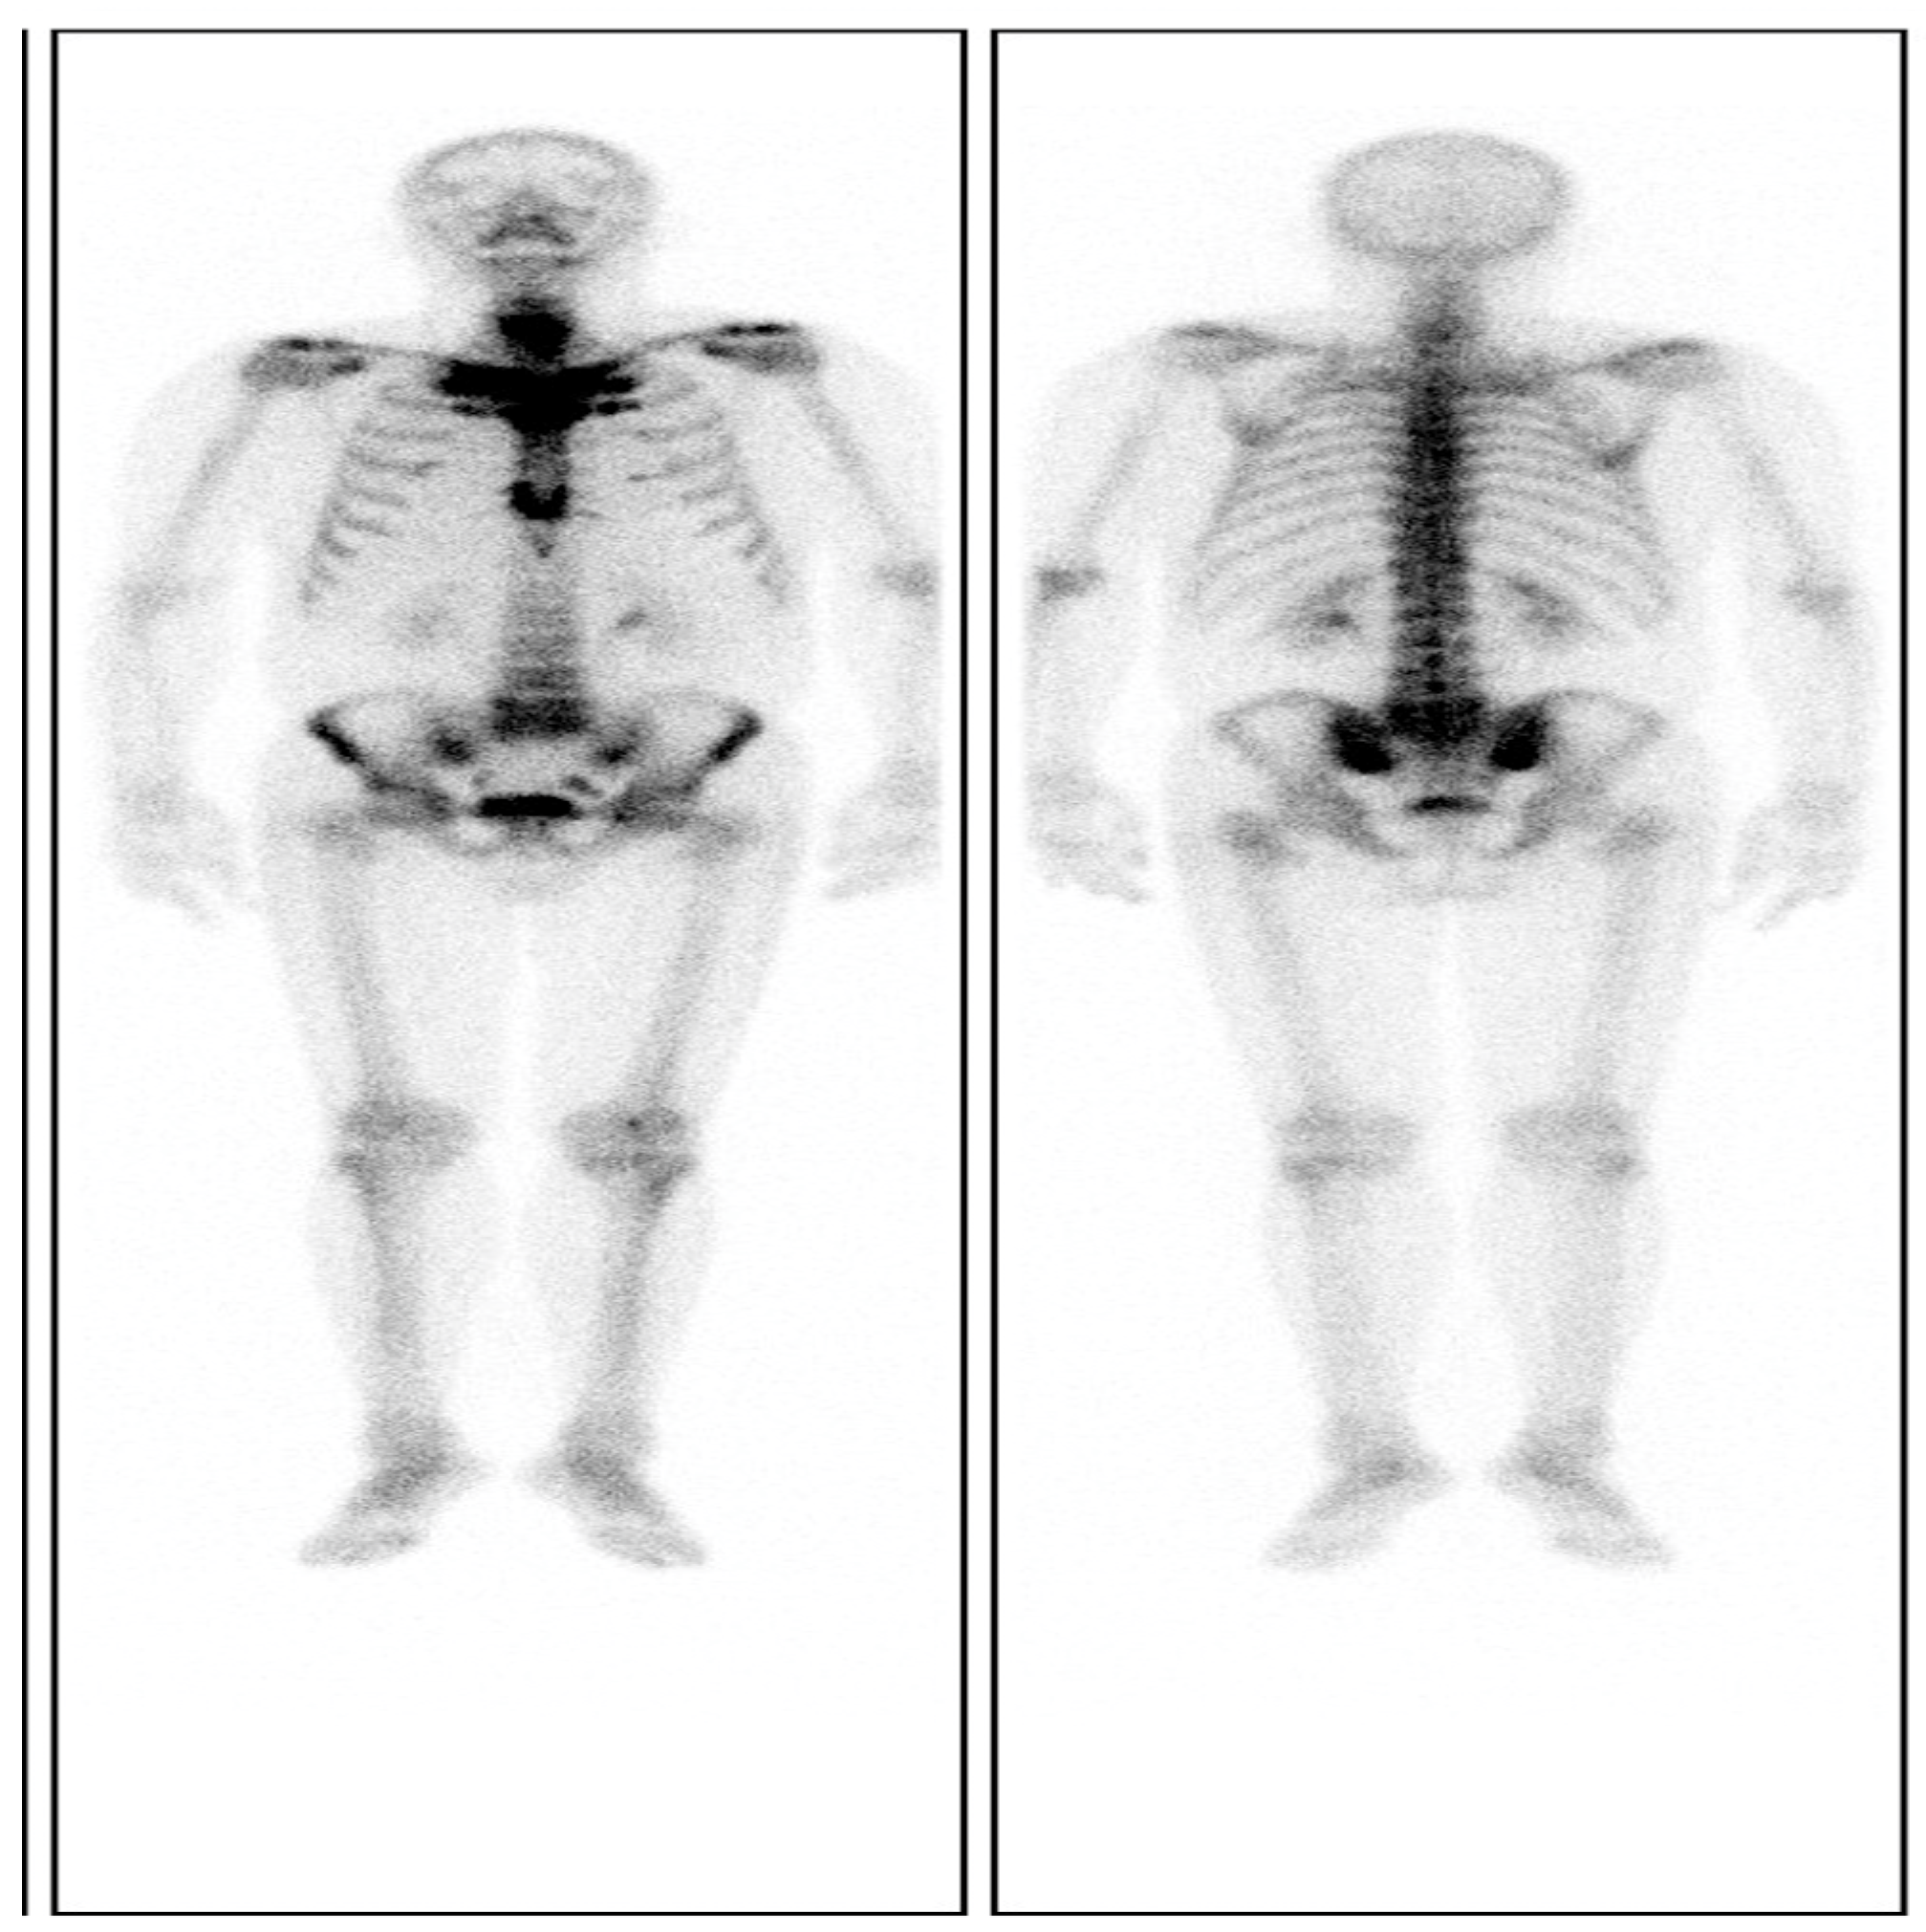

The skin lesions were diagnosed with palmoplantar pustulosis (PPP) after consultation with dermatologists. Notably, a chest CT image showed obviously enlarged sternoclavicular joints with marked hyperostosis and osteosclerosis (Figure 2C), as indicated by the characteristic “bull’s head sign” [8]. A 99Tcm-methylene diphosphonic acid (99Tcm -MDP) single-photon emission computed tomography (SPECT) whole-body bone scan revealed a remarkable radioactive accumulation in the cervical vertebra, sternoclavicular joint, first anterior rib, sternum, and bilateral sacroiliac joints (Figure 3). Thereby, the diagnosis of SAPHO syndrome could be established on the basis of comprehensive clinical assessment.

Figure 3.

A 99Tcm-MDP SPECT whole-body bone scintigraphy revealing a remarkable accumulation in the cervical vertebra, sternoclavicular joint, bilateral first anterior rib, sternum, and sacroiliac joint due to inflammatory bone changes.

In this case, the patient presented typical manifestations of SAPHO syndrome: pain in the anterior chest wall, bone inflammation on SPECT of whole-body bone scanning, “bull’s head sign” on chest CT, PPP on the skin, and plaque psoriasis. After ruling out bone neoplasms and infectious inflammation, the patient was diagnosed with SAPHO syndrome according to the diagnostic criteria for SAPHO syndrome proposed by Kahn and Khan [10]. SAPHO syndrome is prone to misdiagnosis for a variety of atypical manifestations, and due to confusion with many diseases including AS, bone tuberculosis, and bone neoplasms. The primary dilemma is that the first symptoms vary among patients with SAPHO syndrome that hinder differential diagnosis. Furthermore, the lack of awareness of manifestations among clinicians can also lead to the underestimated diagnosis of SAPHO syndrome. Therefore, if patients are suspicious of SAPHO syndrome, they are recommended for local image examination and a whole-body bone scan to detect potential lesions and substantiate definite diagnosis.

At present, although there are no specific markers for SAPHO syndrome evaluation, ESR and CRP may increase during the active phase [15]. In the present case, ESR and hs-CRP were significantly elevated at admission, which indicated the active stage of SAPHO syndrome; levels were reduced to normal levels after treatment, suggesting remission of the disease. Therefore, it is worth monitoring the changes in ESR and hs-CRP to evaluate the progression and guide the management of SAPHO syndrome [15]. Image examination is essential for the diagnosis, evaluation, and treatment of SAPHO syndrome [5,16]. A 99Tcm-MDP whole-body bone scintigraphy is highly appreciated as the preferred image test in the diagnosis of SAPHO syndrome for its high sensitivity in detecting the involvement of bones and joints [16]. In particular, when the sternoclavicular joint, the first sternocostal joint, and the sternocostal–shank junction are involved simultaneously in patients with SAPHO syndrome, the typical “bull’s head sign” emerges, characterized by enhanced radioactive accumulation [15]. However, only approximately 20% of patients with SAPHO syndrome manifest the “bull’s head sign” [17]. Additionally, the patient showed hyperplastic hypertrophy lesion at the sternoclavicular joint on chest CT, and he was unequivocally diagnosed with SAPHO syndrome. Noticeably, image tests are necessary for the diagnosis and evaluation of SAPHO syndrome, and they should be recommended in all suspicious patients.